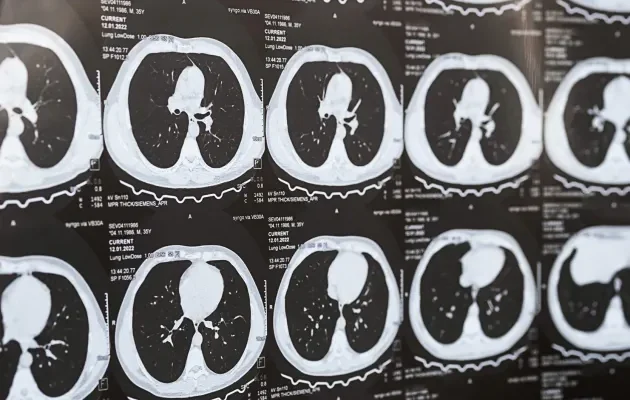

Akciğer sertleşmesinin teşhisi, hastanın medikal öyküsünün ve fiziksel muayenenin yanı sıra, bir dizi tanı testi ile konulabilir. Bu testler arasında göğüs röntgeni, yüksek çözünürlüklü bilgisayarlı tomografi (Akciğer BT), pulmoner fonksiyon testleri, oksijen desatürasyon testleri ve gerekirse akciğer biyopsisi bulunur. Akciğer tomografisi, akciğerlerdeki fibrozisi ve desenini detaylı olarak gösterirken, pulmoner fonksiyon testleri akciğer kapasitesi ve solunum fonksiyonlarının ne ölçüde etkilendiğini değerlendirir. Tanı süreci, hastalığın altında yatan nedeni belirlemeye ve diğer benzer akciğer hastalıklarından ayırt etmeye yardımcı olur.

- Yüksek Çözünürlüklü Bilgisayarlı Tomografi (Akciğer Tomografisi): Akciğerlerin ayrıntılı görüntülerini sağlar ve fibrozisin varlığını, desenini ve yaygınlığını belirlemekte özellikle yararlıdır.